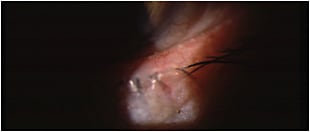

» Figure 1. MGD with lid inflammation and inspissated glands.